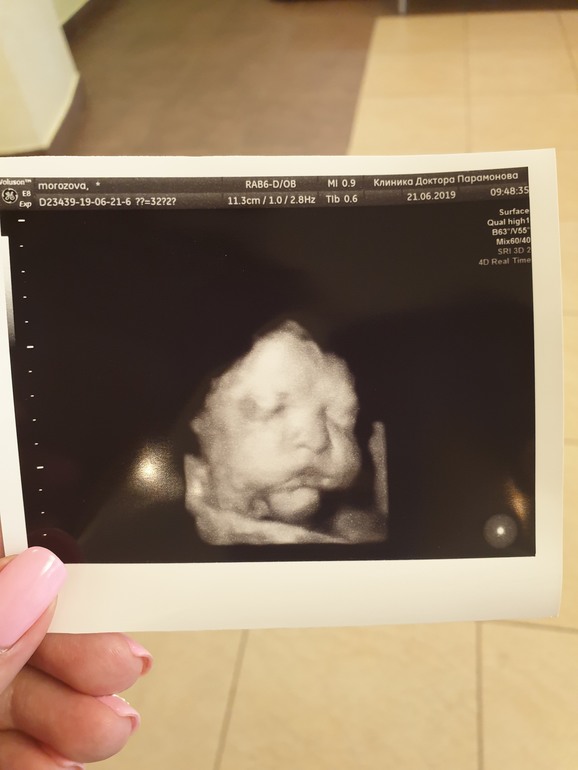

3й скрининг пройден. 32 Нед 3 дня (фото)

Фото такое же первое сегодня было, потом переделали) Мы тоже на УЗИ 3д ходили в 28 недель, пуповина тоже по передней стенке, еще и руки в рот тянула, но потом все таки увидели лицо)))